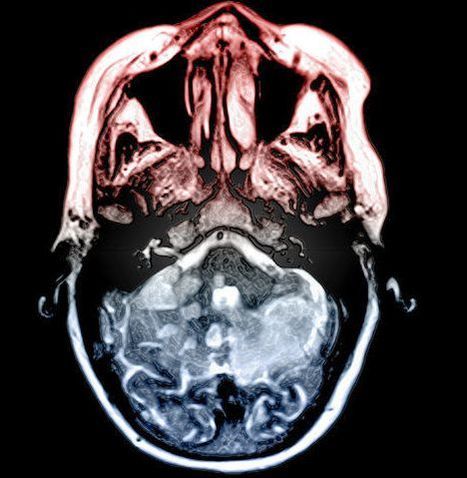

Bilateral infarcts in the middle cerebellar peduncle. 80-year-old man with ataxia and vertigo. A. FLAIR image shows a hyperintense lesion in the left middle cerebellar peduncle to cerebellar hemisphere due to DAI. ... Access Doc